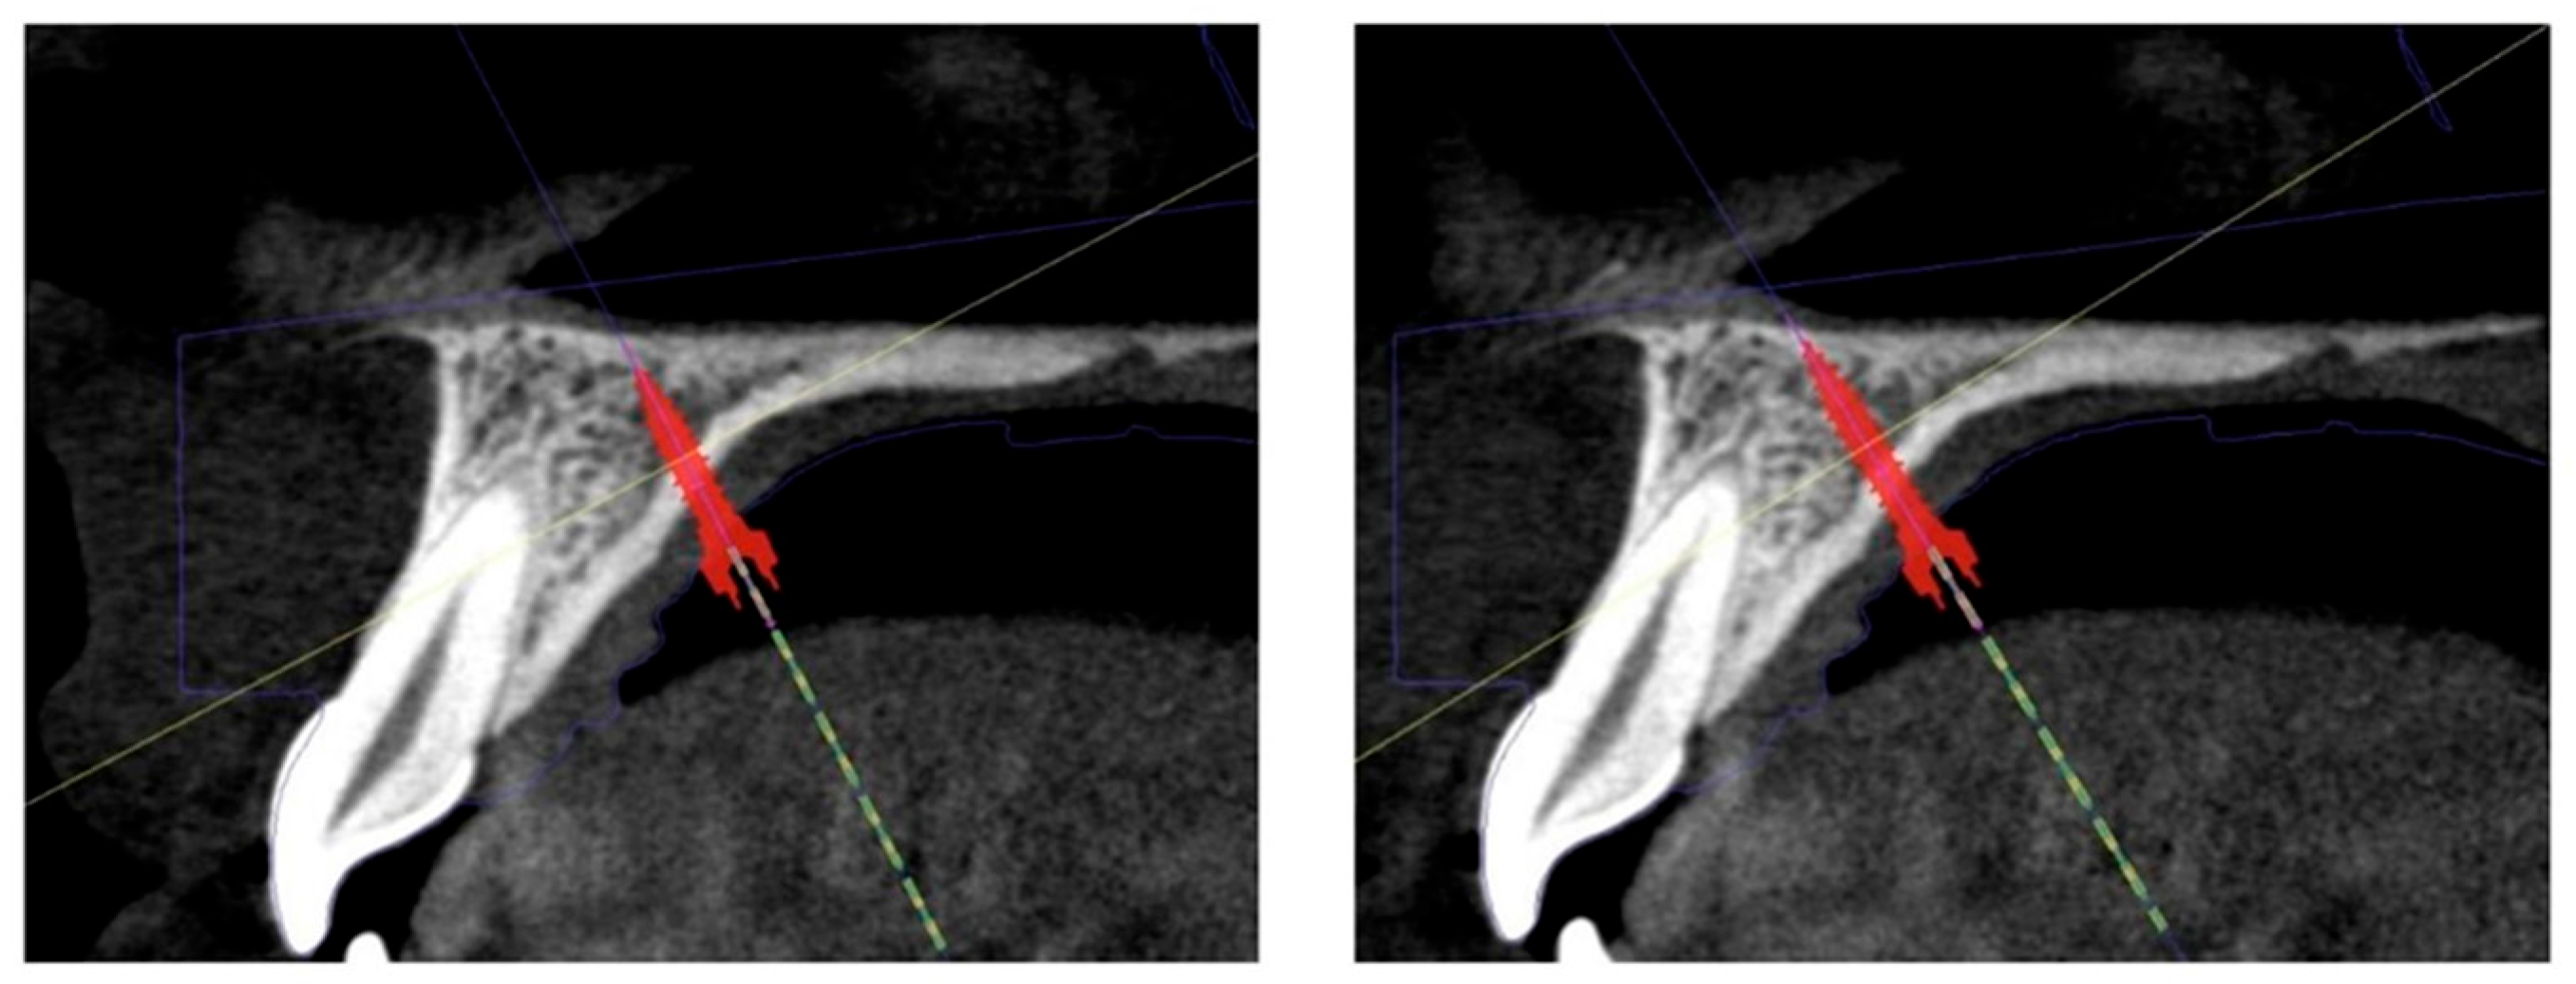

- The Benefit system introduced by Dr. Benedict Wilmes et al. in 2008 (Benefit system, PSM Medical Solutions, Tuttlingen, Germany) that uses two mini-implants placed in the anterior zone of the palate behind the second palatal rugae and arms on each side soldered to the molar bands [27]. An example of a 3D simulation for the anterior positioning of the two mini-implants, performed for a patient from our clinic, can be seen in Figure 1.